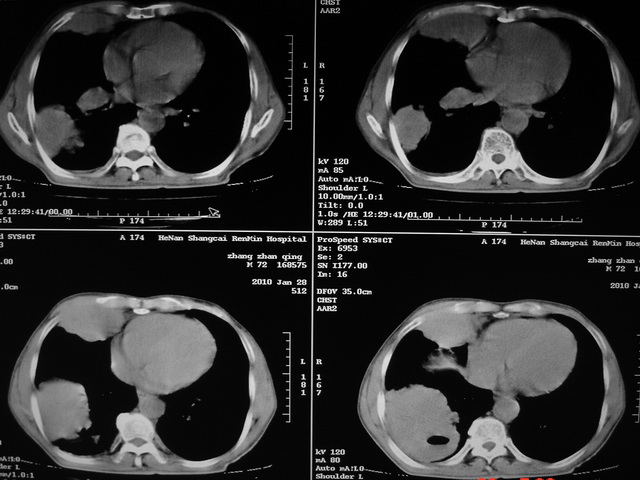

标题: CT24386:M 72岁农民 右侧胸痛6月余,咳嗽,无发热、咯血等 [打印本页]

xx m 72岁农民 右侧胸痛6月余,咳嗽,无发热、咯血等

右下周围型肺癌,并右肺门、纵膈淋巴结、内乳淋巴结转移,右胸膜转移累及前胸壁。鉴别:脓肿、tb、淋巴瘤。病理类型可能为大细胞型。

这个病人有点复杂了,上纵隔像是占位,右肺下叶见壁光整厚壁空洞加液平,像是肺脓肿,中叶病灶牵涉到胸膜及胸壁,形态看像是炎性病变,总之不能除外恶性病变,还是穿刺或增强后再说。

右下周围型肺癌。偏心空洞形成伴感染。

右下周围型肺癌伴转移

支持2搂,考虑右肺下叶周围性肺癌伴肺门及纵膈淋巴结转移!右侧前纵膈病灶,还是一元论考虑为胸壁或胸膜转移瘤。

支持 右肺下叶周围型肺癌并右肺门、纵膈淋巴结、内乳淋巴结转移,右胸膜转移累及前胸壁。